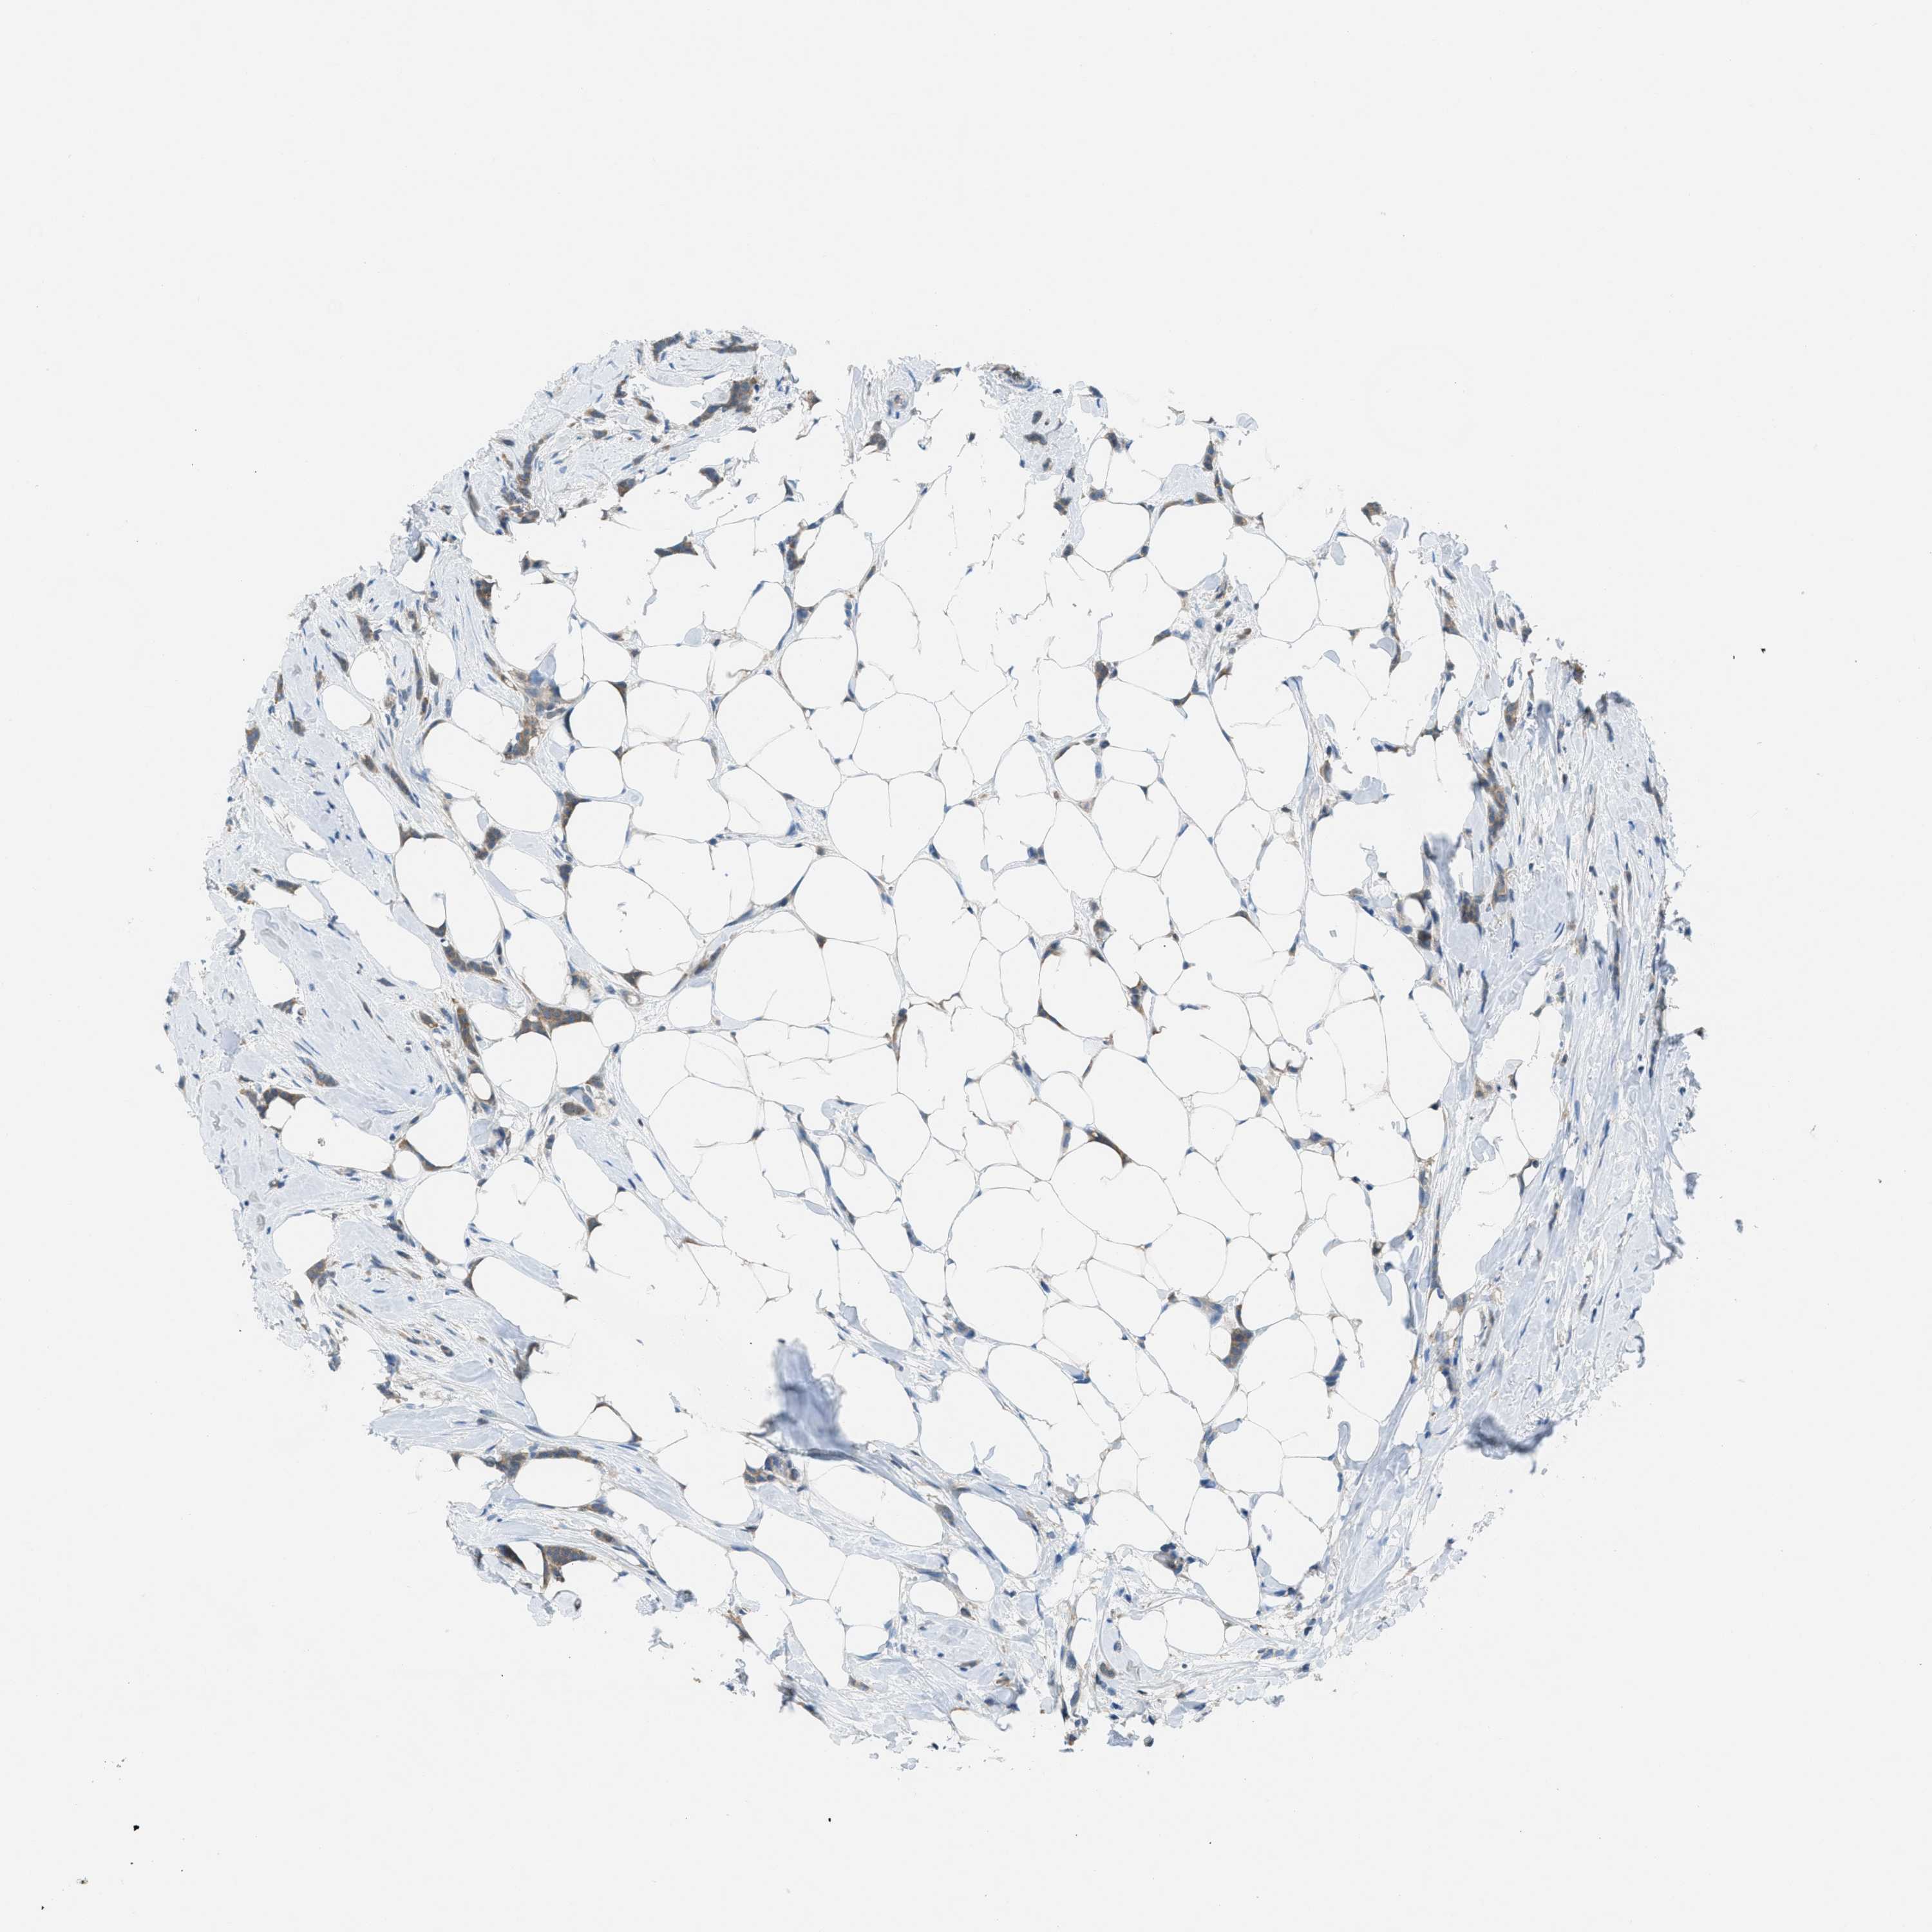

CANCER BREAST CANCER Show tissue menu

BRCA TCGA BRCA VALIDATION PROTEIN EXPRESSION